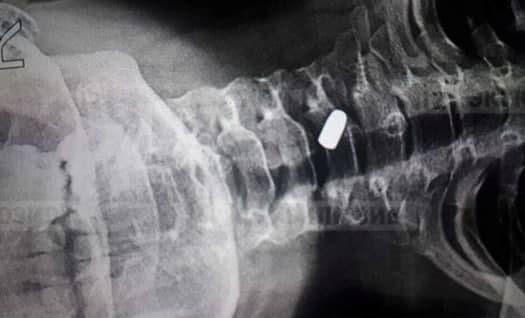

⁉️ Неизвестный в Ленобласти выстрелил в детей, которые играли на детской площадке. В результате десятилетний мальчик получил ранение в шею. Сейчас ребёнок в больнице. Задело только мягкие ткани, так что угрозы жизни нет.

Преступника до сих пор ищет полиция. Оружие, из которого он стрелял, не установлено. Причины такой жестокости — тоже